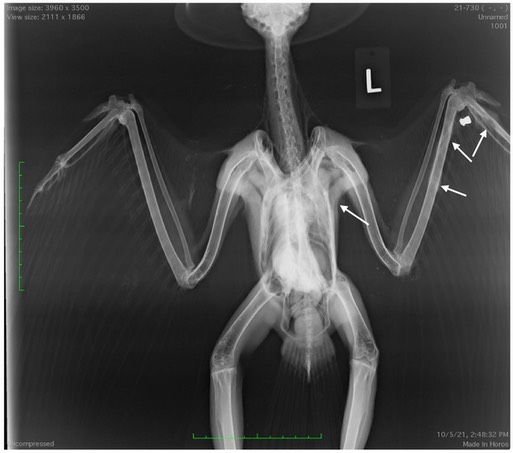

Gunshot Red-tailed Hawks 21-730 and 21-734

The second radiograph shows a very large callous at the top of the right humerus. The hawk was probably shot at least three weeks ago, explaining why the hawk is so thin. If you look closely you can see small metal fragments below the arrow. The two birds were shot with different types of projectiles. Both caused major damage. We are conducting physical therapy to increase range of motion in the first hawk’s left wrist in the hope that it will be releasable. The second hawk was euthanized because it would never be able to fly.